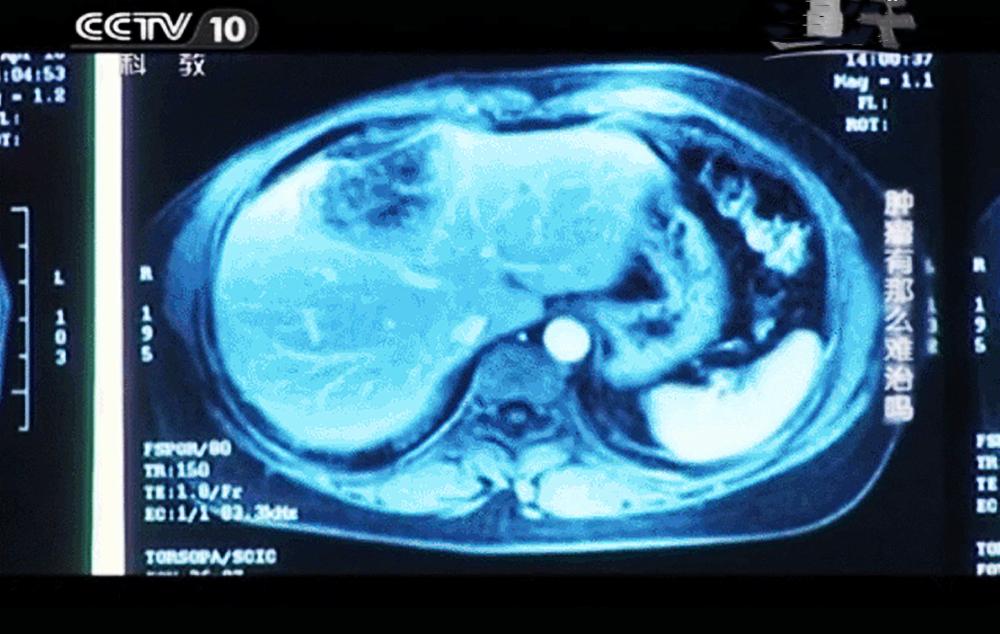

图源:CCTV-10

在一次出现疼痛后去医院复查,结果得知肝脏上出现了一个直径约为8厘米的肿块。这无疑是雪上加霜,患者及家人都认为没有希望了。

在使用细胞免疫疗法一段时间后,患者感觉疼痛明显缓解,肝脏转移的肿瘤也出现缩小,身体的免疫功能也逐步提升。对其连续4个月的复查CT结果对比,转移到肝脏的肿瘤从8厘米已经缩小到了2.5厘米。肿瘤标记物指标也在正常范围,这表明免疫细胞已经逐步在清除体内的癌细胞。